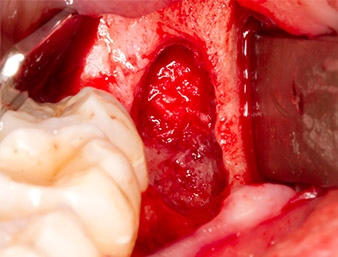

The tissue above the root remnant was not completely ossified and consisted for the most part of granulation tissue modified by inflammation (Fig.4).

Granulation tissue

Fig. 4: Two Langenbeck retractors and a raspatorium expose the operating area. Granulation tissue of the incompletely healed first osteotomy can be seen.